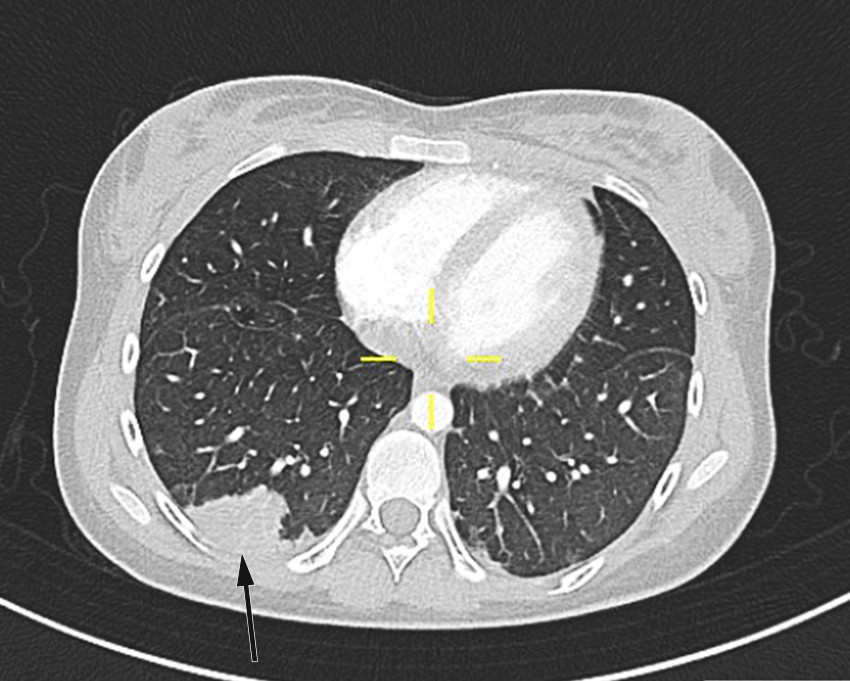

Pasienten fikk smerter i venstre del av toraks på dag 2. CT toraks og abdomen viste funn forenlig med septiske embolier i begge lunger og mulig infarktkomponent i høyre underlapp (figur 2, figur 3). I tillegg var det lett forstørret lever og milt, periportalt ødem samt små mengder fri væske i bekkenet (mulig fysiologisk). Det var også beskrevet mistanke om tromber i vena subclavia og vena axillaris på høyre side. Dag 3 så man oppvekst av penicillinfølsomme Streptococcus anginosus i blodkultur. Serologiske prøver viste svakt positivt Epstein-Barr-virus (EBV)-viralt kapsidantigen (VCA)-IgG, svakt positivt EBV-VCA-IgM og negativt EBV-EBNA-IgG. Intravenøst benzylpenicillin og klindamycin samt antikoagulasjonsbehandling med lavmolekylært heparin (enoksaparin) ble kontinuert.